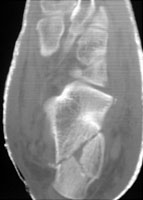

- Click on the image for a larger versionCAxial CT. This image of both feet shows a calcaneal fracture. The normal size is included for comparison.

- Click on the image for a larger versionDAxial CT. This image better demonstrates the comminuted calcaneal fracture.